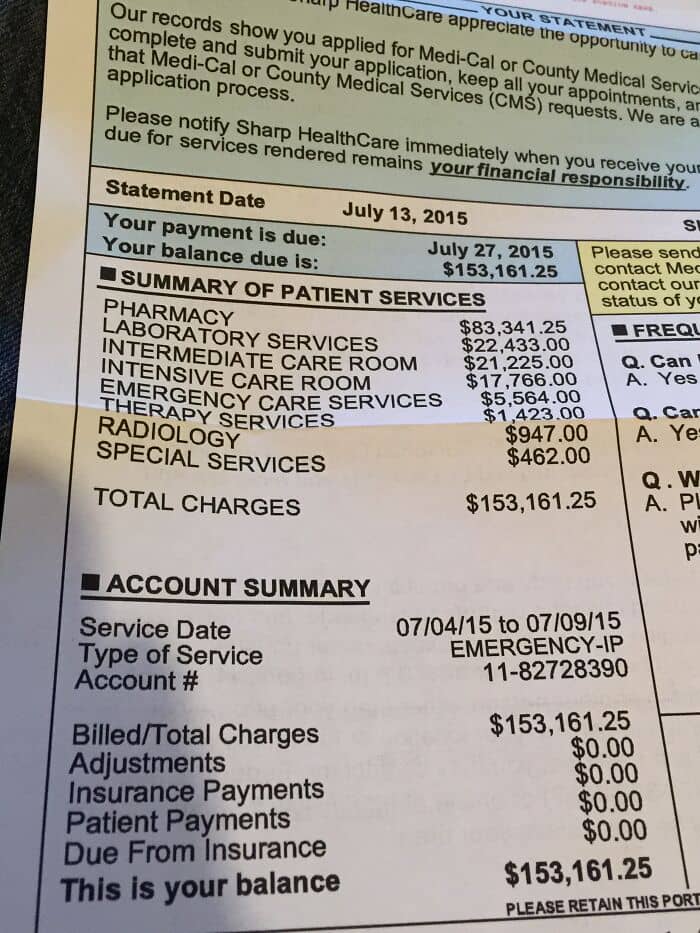

#14 I Was Billed Over $2m For A Week In The Hospital

#15 Is This A Joke? Someone Actually Has To Pay This

#45 My Kid Was In The Hospital For 3 Days Due To Pneumonia. Thank God We Have Insurance. I Don’t Know How Anyone Can Still Defend U.S. Healthcare